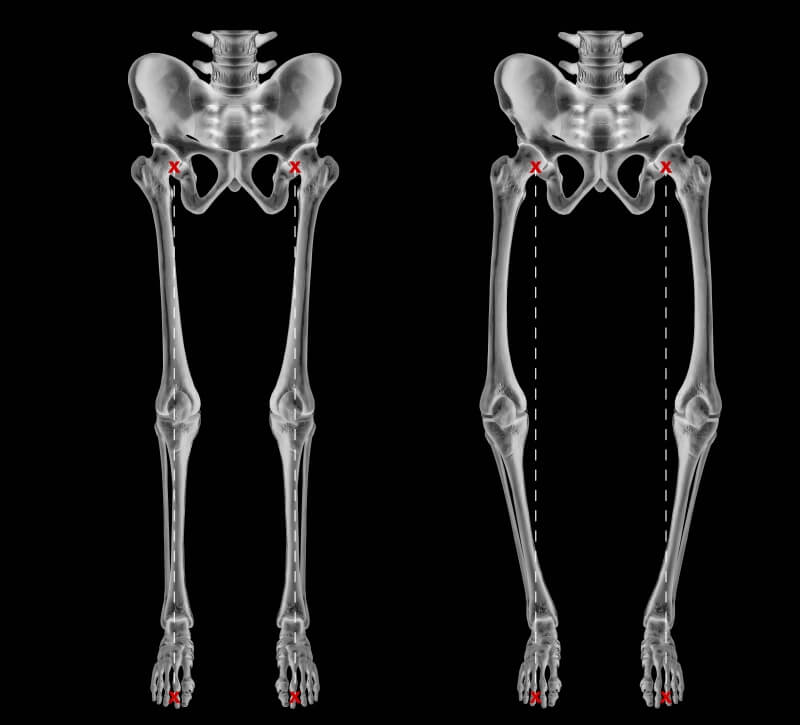

Bow legs, also known as genu varum, is a condition where the legs appear bowed outwards when standing. This condition can cause discomfort, pain, and even difficulty walking. In severe cases, surgery may be required to correct the alignment of the legs. In this article, we will discuss the causes, symptoms, and treatment options for bow legs, including the various surgical procedures available.

Knock Knees, also known as genu varum, is a condition where the legs appear bowed outwards when standing. This condition can cause discomfort, pain, and even difficulty walking. In severe cases, surgery may be required to correct the alignment of the legs. In this article, we will discuss the causes, symptoms, and treatment options for Knock Knees, including the various surgical procedures available.